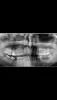

Да, действительно, слева у Вас нет зуба мудрости и не будет. На ОПТГ видно, что зачаток этого зуба отсутствует.

Справа 8-й зуб рекомендовано удалить. Ему не достаточно места в зубной дуге, он корнем упирается в дистальный корень 7-го зуба, тем самым травмируя его. Не исключено, что именно этот фактор играет роль в беспокойстве зуба.